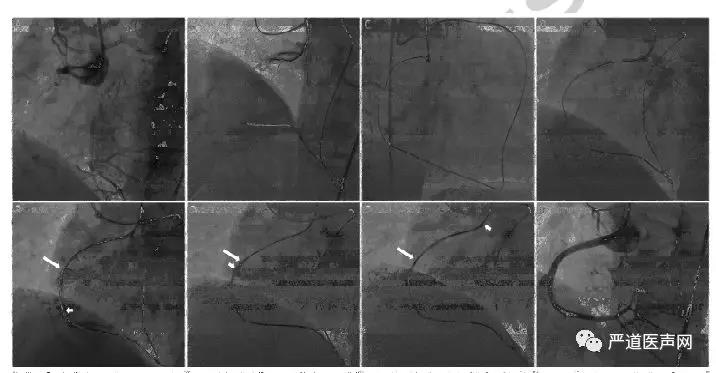

病例一:67岁男性,有严重心绞痛,危险因素包括高血压和吸烟,当地医院拟开通RCA CTO病变失败。使用6 Fr SAL1.0 SH 指引导管(Medtronic) 和 7 Fr EBU 3.5 指引导管(Medtronic)(图a)。综合分析CTO病变的形态和侧枝循环后直接尝试逆向技术。Sion导丝(Asahi intecc)和150cm Corsair (Asahi intecc)微导管通过侧支,尝试逆向CART技术(b-d)。Guidezilla™延长导管尽可能向远端送,迎接逆向CART技术的导丝(e)。球囊扩张后,逆向导丝(短箭头)成功置入Guidezilla™延长导管,RG3导丝(Asahi intecc)成功体外化(g)。复查造影可见RCA CTO病变开通(h)。